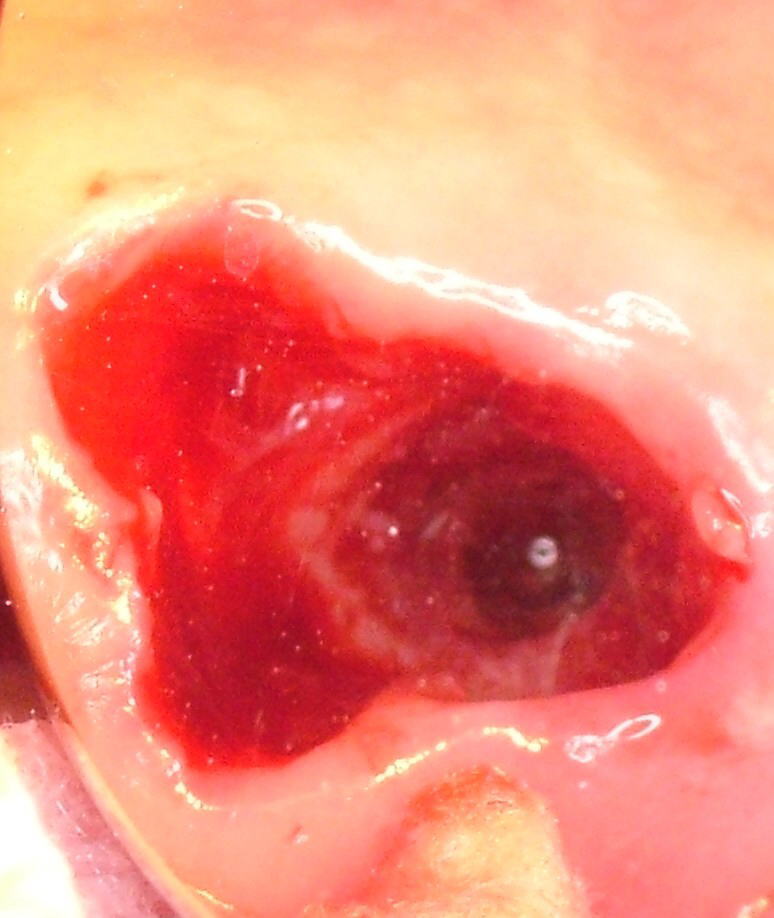

下の写真は歯根膜炎を長年にわたって放置したために、上記のようなことが起こり、抜歯したところ、上顎洞に通じてしまっていたケースです。

右上大臼歯の歯根端から上顎洞に通じています 右上大臼歯の歯根端から上顎洞に通じています